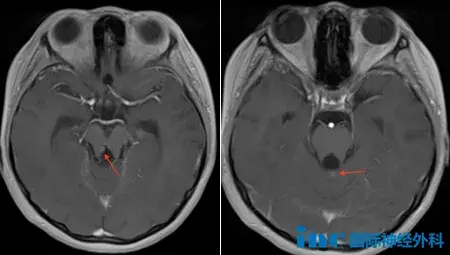

一开始孩子只是爱摔倒,谁曾想后来竟然恶化到偏瘫了! 一想到6岁的女儿以后很可能不良于行,身为母亲的吴女士满心懊悔:当初没有医生告诉我们能安全手术的,这个脑干胶质瘤手术风险太...

脑干胶质瘤到底怎么回事?有治好的没?这个病到底多严重?现在在医院,无知带来了无限的恐惧。一名脑干胶质瘤病友在网上发了这样一个问题,引来了无数胶质瘤乃至脑干胶质瘤患者及家属...